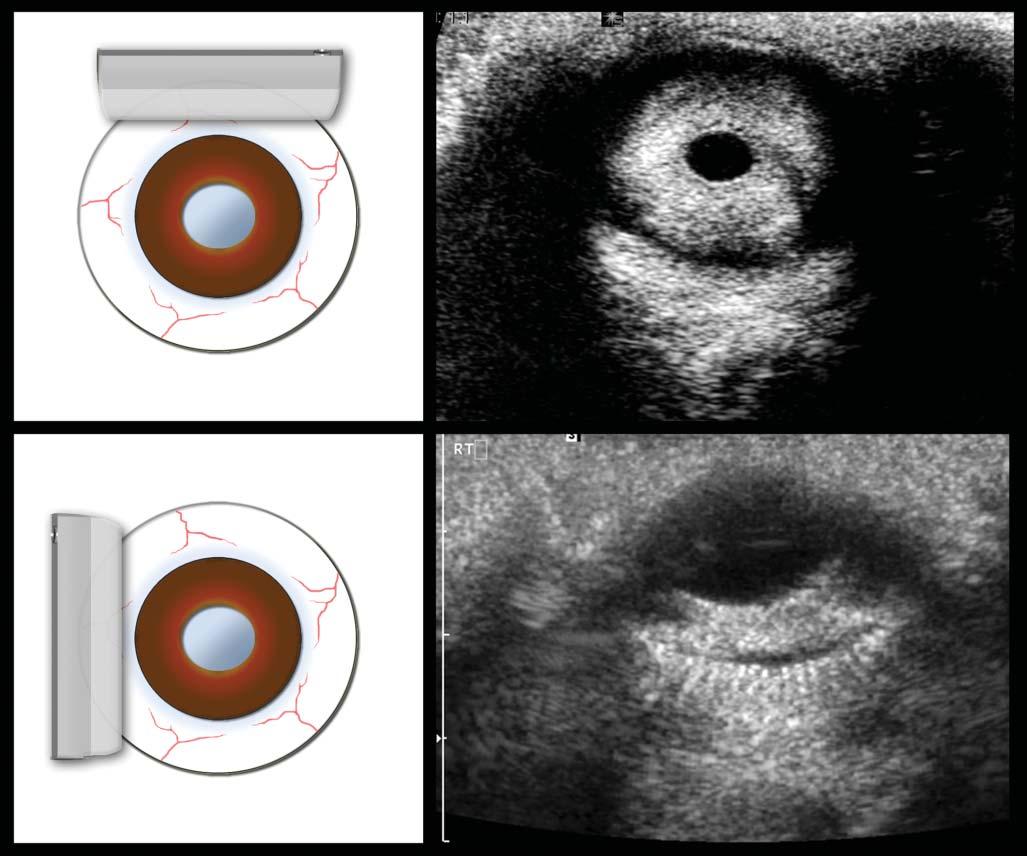

UltrasoundProbes andResolution

Ultrasoundprobes varyinconfigurationsforspecific needs(Figure1.4).Curvedlinearprobes,alsocalled convexormicroconvex,haveoneorseveralrowsof piezoelectriccrystalsalignedalongaconvexsurface, withvaryingbeamsandtracks.Theseprobesproduce

atriangularimagebecauseofthediverginglinesof ultrasoundwavestheygenerate.Themainassetsof thistypeofprobeareitssmallerfootprintanditslarge scanningfield,makingittheidealprobeforassessing theabdomen,particularlythecranialportionalong

theribcage.Thepiezoelectriccrystalsofthelinear probesaredistributedalongaflatsurface,producing arectangularscanfield.Thephaseintervalofthe impulsionscanalsoproduceatrapezoid-shaped image,allowingittocoveralargersurface.Thisis

Figure1.4. Practicalultrasoundtransducers. Mostultrasoundunitsareequippedwithconvex (A,B) andlinear (C) electronictransducerswithvariablefrequencies.Amacroconvexprobe (A) offeringlowerfrequencies(3–8MHz)isbestsuitedfor theabdomenoflargedogs,whereasamicroconvexprobe (B) ofhigherfrequencyandsmallerfootprintispreferredforthe abdomenofsmallpatientsandwhenonlyasmallacousticwindowisavailable(e.g.,theintercostalapproachofalunglesion). Ahigh-frequency(10–18MHz)linearprobe (C) ismostusefulforassessingsuperficialstructuresonarelativelywideandflat surface(e.g.,assessingbowelsinacat,bicepstendoninadog).Aphasedarraytransducer (D) offersasmallflatfootprintand isidealforechocardiography.

especiallyusefulwhenevaluatingsuperficialorgans whosediametermaybegreaterthanthewidthofthe scannedarea,suchasthekidneysandspleen.The lengthoftheprobe’sfootprintindicatesthewidthof theareaitscans.